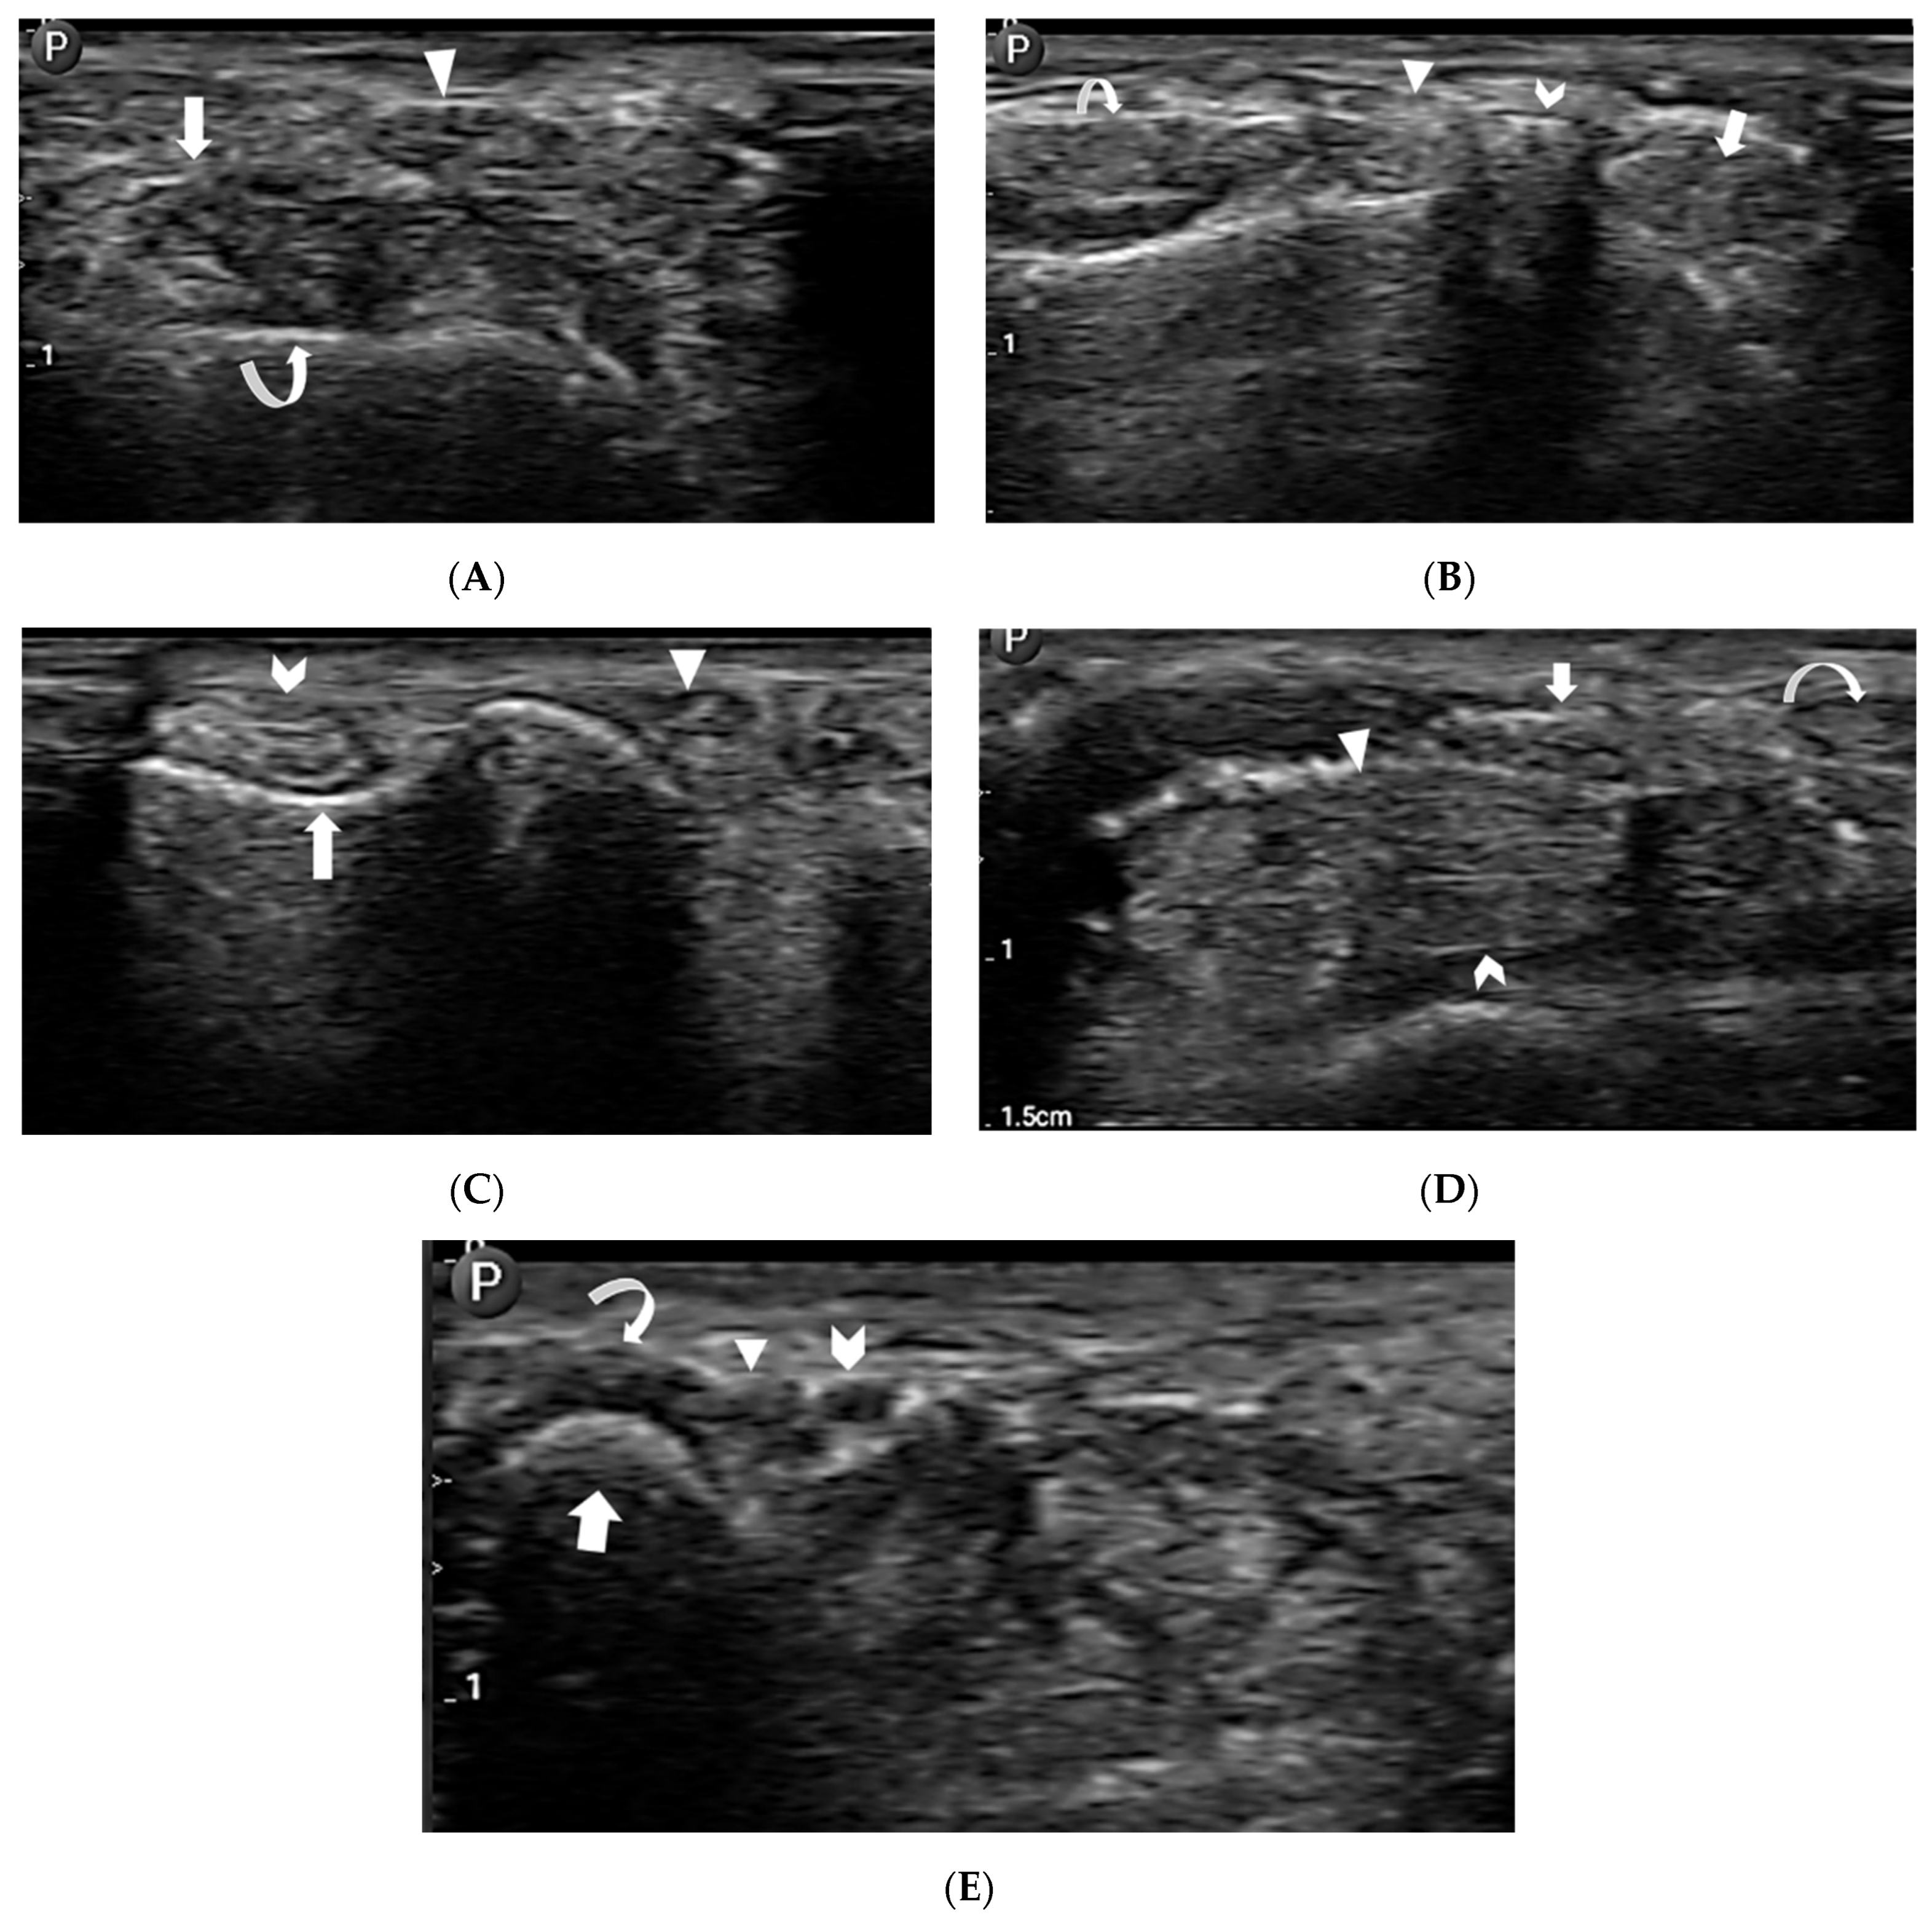

- Extensor tendon compartments:

- First extensor compartment—extensor pollicis brevis and abductor pollicis longus tendons (Figure 5A).

- Second extensor compartment—extensor carpi radialis longus and brevis tendons (Figure 5B).

- Third extensor compartment—extensor pollicis longus tendon (Figure 5A,B).

- Fourth extensor compartment—extensor digitorum longus tendons (Figure 5B).

- Fifth extensor compartment—extensor digiti minimi tendon (Figure 5C).

- Sixth extensor compartment—extensor carpi ulnaris tendon (Figure 5C).

- Flexor tendons:

- Median nerve (Figure 5D).

- Guyon’s canal contents:

- Bony anatomy: